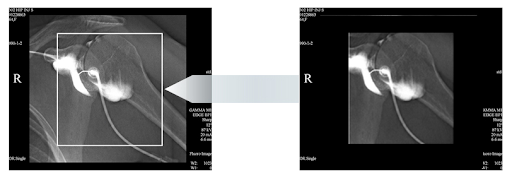

- Увеличенные возможности визуализации

- Отличное качество изображения

Большой плоский детектор 17 ”x 17” позволяет:

- Уменьшить дозу и сократить время обследования

- Увеличить анатомическое покрытие для более полного обзора и уменьшить потребность в нескольких изображениях